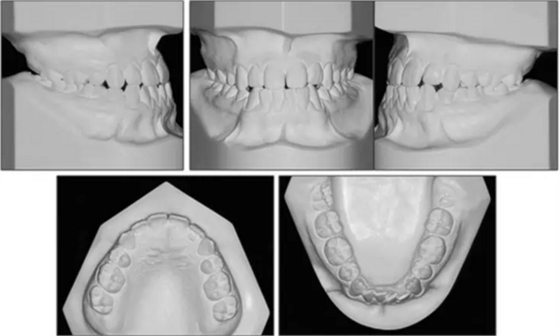

口內(nèi)相示:尖牙、磨牙完全I(xiàn)II類(lèi)關(guān)系,覆蓋2mm,覆合端端關(guān)系,上頜中線左偏2mm,下頜牙列擁擠5mm。

X片示:III類(lèi)頜骨關(guān)系(ANB,-4°;Wits值,-10mm);上切牙前突、唇傾,下切牙內(nèi)縮(1:NA, 8mm、35°; 1:NB, 4mm、15°;IMPA, 77°);綜合考慮咬合平面角、下頜平面角、Y軸角,判定為水平生長(zhǎng)型;McNamara分析示,上頜相對(duì)顱底后縮(Co-A, 88mm; A-NPerp, 4mm),下頜相對(duì)顱底前突(Co-Gn, 135mm; Pog-Nperp, 10mm),上下頜骨不調(diào)(Co-A–Co-Gn, 47mm);此外,患者4個(gè)第一前磨牙缺失。